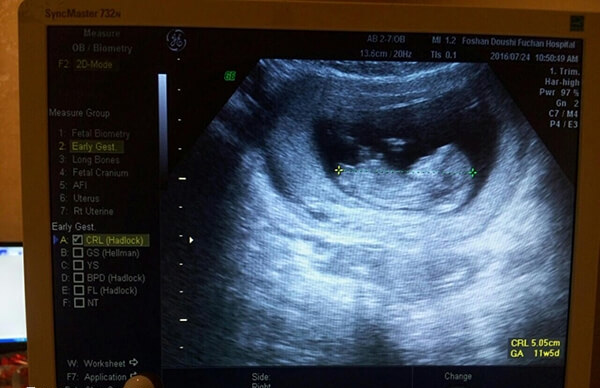

2、B超检查

试管移植14天后的患者,还需要进行腹部B超检查,尤其是如果HCG水平呈阳性,且翻倍比较好的情况下,这时进行腹部B超检查,是为了更好的观察子宫内是否有孕囊存在,并评估孕囊的位置和大小。